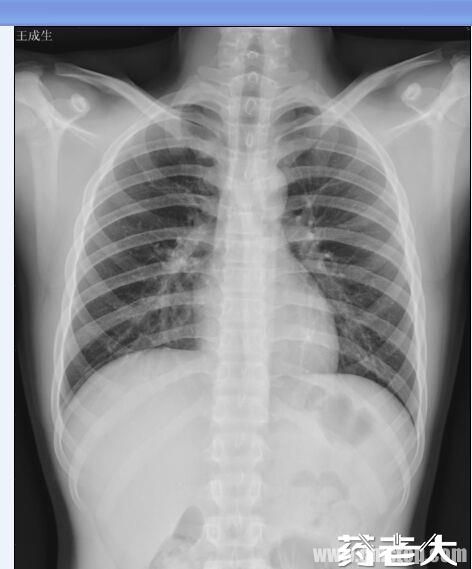

图像清晰,分辨率高,成像细腻;

技术参数:图像分辨率:2400×1440dpi;16bit灰阶成像,呈现完美纯黑像素;兼容DICOM3.0标准,无缝对接影像工作站或PACS;打印机可安装win7系统PC机或服务器;胶片可保存30-50年。

各种检验、体检、超声、三维重建、病理、彩色胶片照相、CR、DR、MRI、RVG、口腔、牙片、眼科影像、红外乳腺、阴道镜、各型光学窥镜与电镜、建模预测等各类医疗报告。